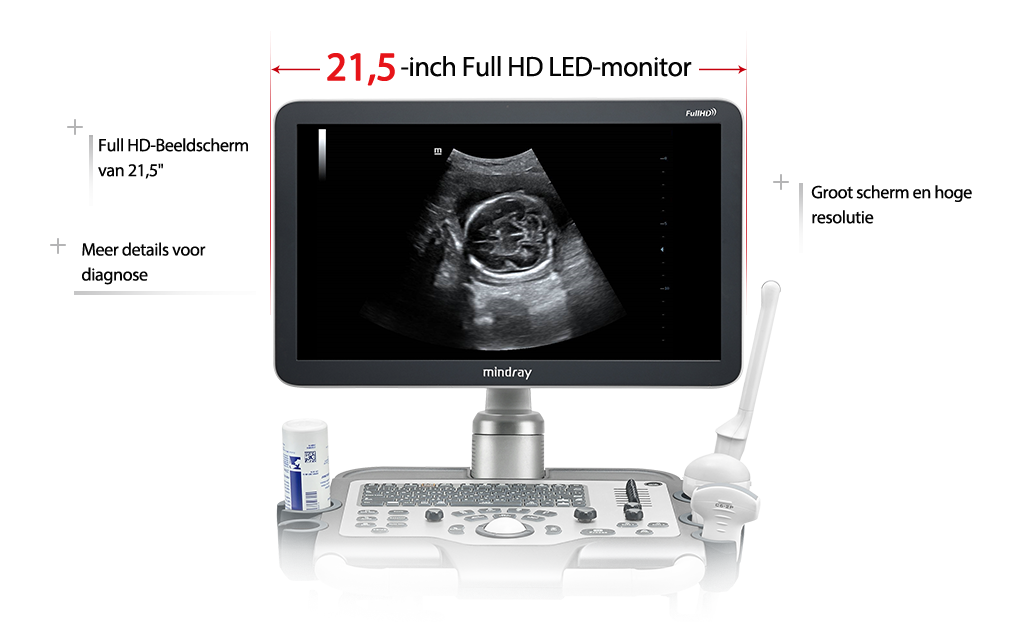

FullHD-laag

Scherm van 21,5 inch:

1920 x 1080, 180 rotatie

FullHD-laag

2

Scherm van 21,5 inch:

1920 x 1080, 180 rotatie